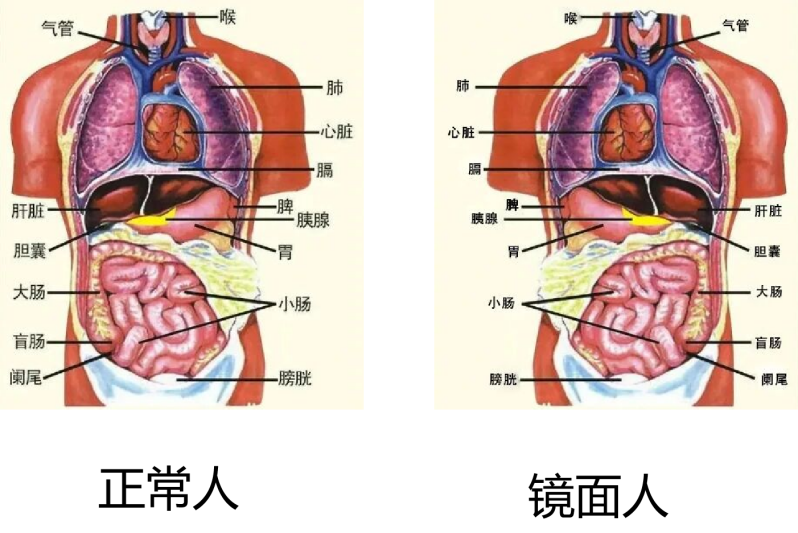

“镜面人”,在医学精准定义里称为“完全性内脏反位”,是一种罕见的先天性生理变异,其发生率低至百万分之一,堪称医学界“大熊猫”。这类患者的内脏器官,包括心脏、肝脏、胃、胆囊、胆管等,如同被一双无形大手完全翻转,与正常人的位置截然相反,仿佛置身于一个镜像交错的神秘世界。这种独特的解剖结构,不仅在日常生活中给患者带来诸多不便,更在疾病治疗,尤其是手术治疗时,为医生布下“迷局”。

上腹部核磁+MRCP影像 (左侧胆囊)